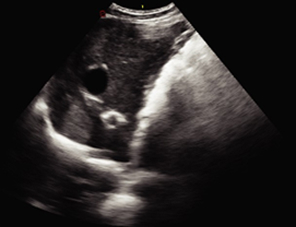

Imágenes Clínicas